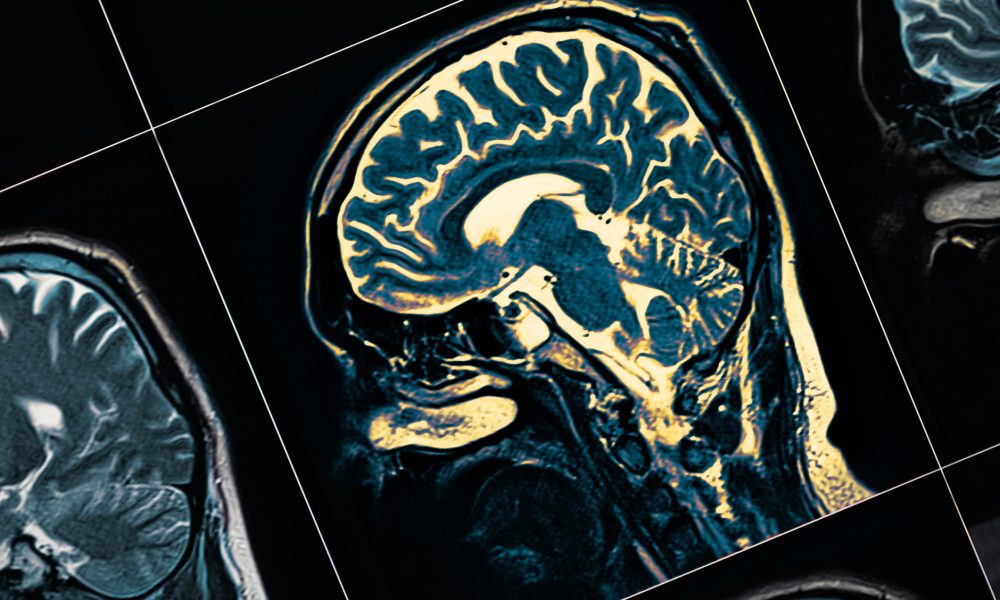

Described as a progressive neurological condition, Parkinson’s Disease directly affects the human nervous system. This disease is caused by the loss of nerve cells in a part of the brain, which becomes progressively damaged over time. Studies have shown that Parkinson’s disease occurs as a result of a combination of genetic and environmental factors.